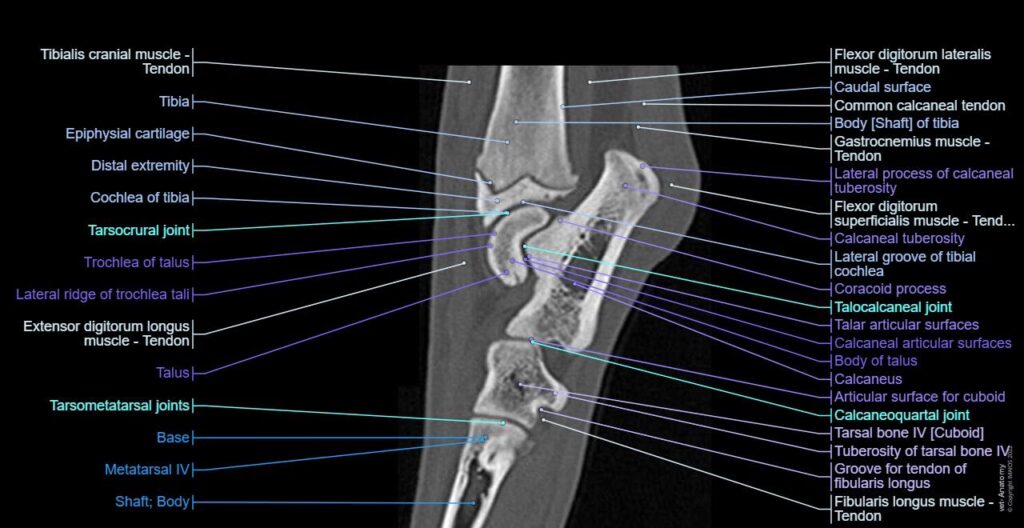

Hvad er Tarsus? En Dybdegående Anatomisk Gennemgang

For at forstå alvoren af en skade er det vigtigt at kende til anatomien. Tarsus er ikke bare et enkelt led, men en avanceret struktur bestående af syv knogler, flere led og et netværk af ledbånd, der arbejder sammen for at give både stabilitet og fleksibilitet.

Tarsalknoglerne er arrangeret i to primære rækker:

- Proksimale række: Denne række, tættest på skinnebenet, består af to store knogler: talus (rullebenet) og calcaneus (hælbenet). Talus er en af de primære vægtbærende knogler, da den danner led med skinnebenet (tibia).

- Distale række: Denne række består af fire mindre, nummererede tarsalknogler (første til fjerde).

Mellem disse to rækker ligger den centrale tarsalknogle, som fungerer som en form for bindeled.

Led og Bevægelse

Tarsus indeholder flere led, men det vigtigste er det tarsocrurale led, som er leddet mellem skinnebenet/lægbenet og talus. Dette er et høj-mobilt led, der står for størstedelen af hasens bøjning og strækning. De øvrige led i tarsus er lav-mobile og bidrager primært med stabilitet og mindre justeringer i bevægelsen.